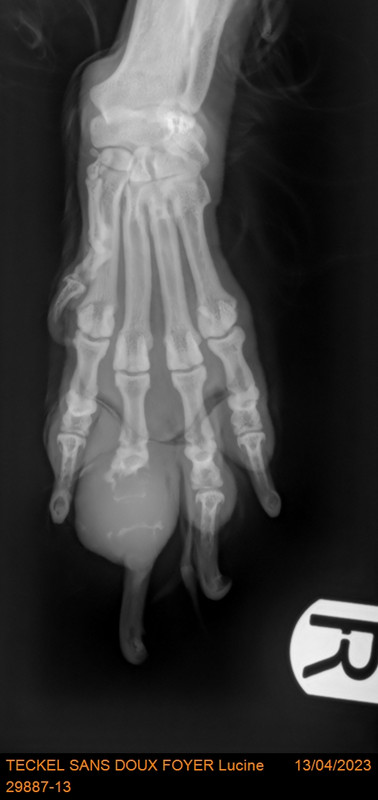

Vouci la radio de Lucille, vous allez comprendre.

[Image: 29887-13-TECKEL-SANS-DOUX-FOYER-Lucine-2436.jpg]

LUCINE est présentée pour une boiterie du membre antérieur droit. Depuis quelques jours, LUCINE présente une boiterie sans appui du membre antérieur droit. Aucun traumatisme n'a été remarqué.

Boiterie sans appui du membre antérieur droit

Grosseur et douleur à la palpation des phalanges du doigt III du membre antérieur droit Absence d'autre anomalie orthopédique ce jour

1/ Masse digitée distale du doigt III de l’antérieur droit, de caractère agressif avec lyse des phalanges. Un processus tumoral est probable (tumeur unguéal, fibrosarcome…) mais une analyse histologique est nécessaire pour en déterminer la nature avec certitude. 2/ Adénopathie préscapulaire droite réactionnelle ou métastatique.

Conclusion :

LUCILE présente une masse ostéolytique des phalanges du doigt III du membre antérieur droit. Dans ce contexte, une origine infectieuse ou tumorale sont privilégiées. En cas de nature bactériologique, un traitement antibiotique sera mis en place pendant 1 mois minimum. En cas de nature tumorale, un retrait de la masse sera à envisager avec un risque de déhiscence de plaie, de récidive locale ou de boiterie persistante étant donné la retrait de phalanges d'une doigt porteur. Une prothèse ostéo-intégrée au niveau du radius et de l’ulna distal droit pourra également être envisagée. Veuillez nous recontacter d'ici 10 jours afin de connaître les résultats des analyses.